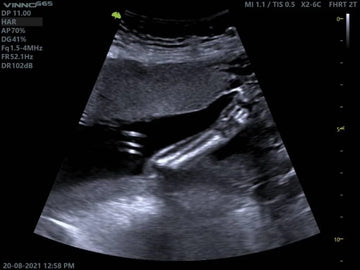

Abdominal ultrasound has become an essential tool in modern veterinary medicine. It is a non-invasive examination that allows veterinarians to observe the internal organs and structures of animals in real time, offering a precise and detailed window for diagnosing a wide variety of pathologies. The image shown here is an example of an abdominal ultrasound examination in which key structures are visualized, allowing for a detailed assessment of the patient's health.

This type of study allows veterinarians to visualize organs such as the liver, kidneys, spleen, pancreas, bladder, and intestines. Through ultrasound imaging, veterinarians can identify changes in the morphology of these organs, the presence of abnormal fluid in cavities, tumors, stones, and other internal problems that would not be detectable through a standard physical examination. Some of the most common diagnoses that can be made include: